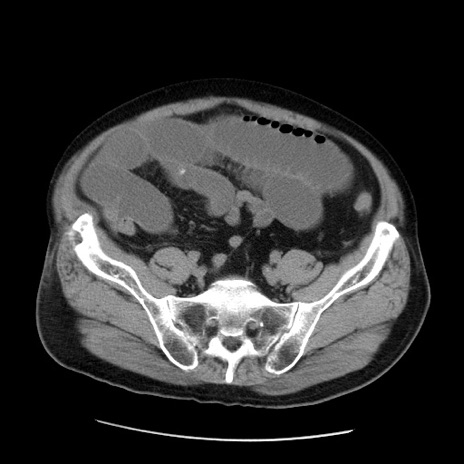

症例20(横断像)

【症例】 60歳代男性

【主訴】 腹部膨満、嘔吐

【現病歴】5日前頃より倦怠感を認め食事量減少し4日前の朝嘔吐、食事摂取困難となった。 3日前近医受診し点滴施行され整腸剤などを処方された。 当日他院を受診し、腹部膨満著明、炎症反応の上昇(CRP10.8、WBC11200)あり、紹介受診となる。

【身体所見】 意識JCS1 受け答えがはっきりしないBP 111/57mHg、 P 67bpm、、BT35.2°C、SpO2 97%(RA)、 腹部:膨隆、打診で鼓音あり、全体的に圧痛有り、腸蠕動音(-)、反跳痛ははっきりせず。

【データ】WBC 11400、CRP 14.20